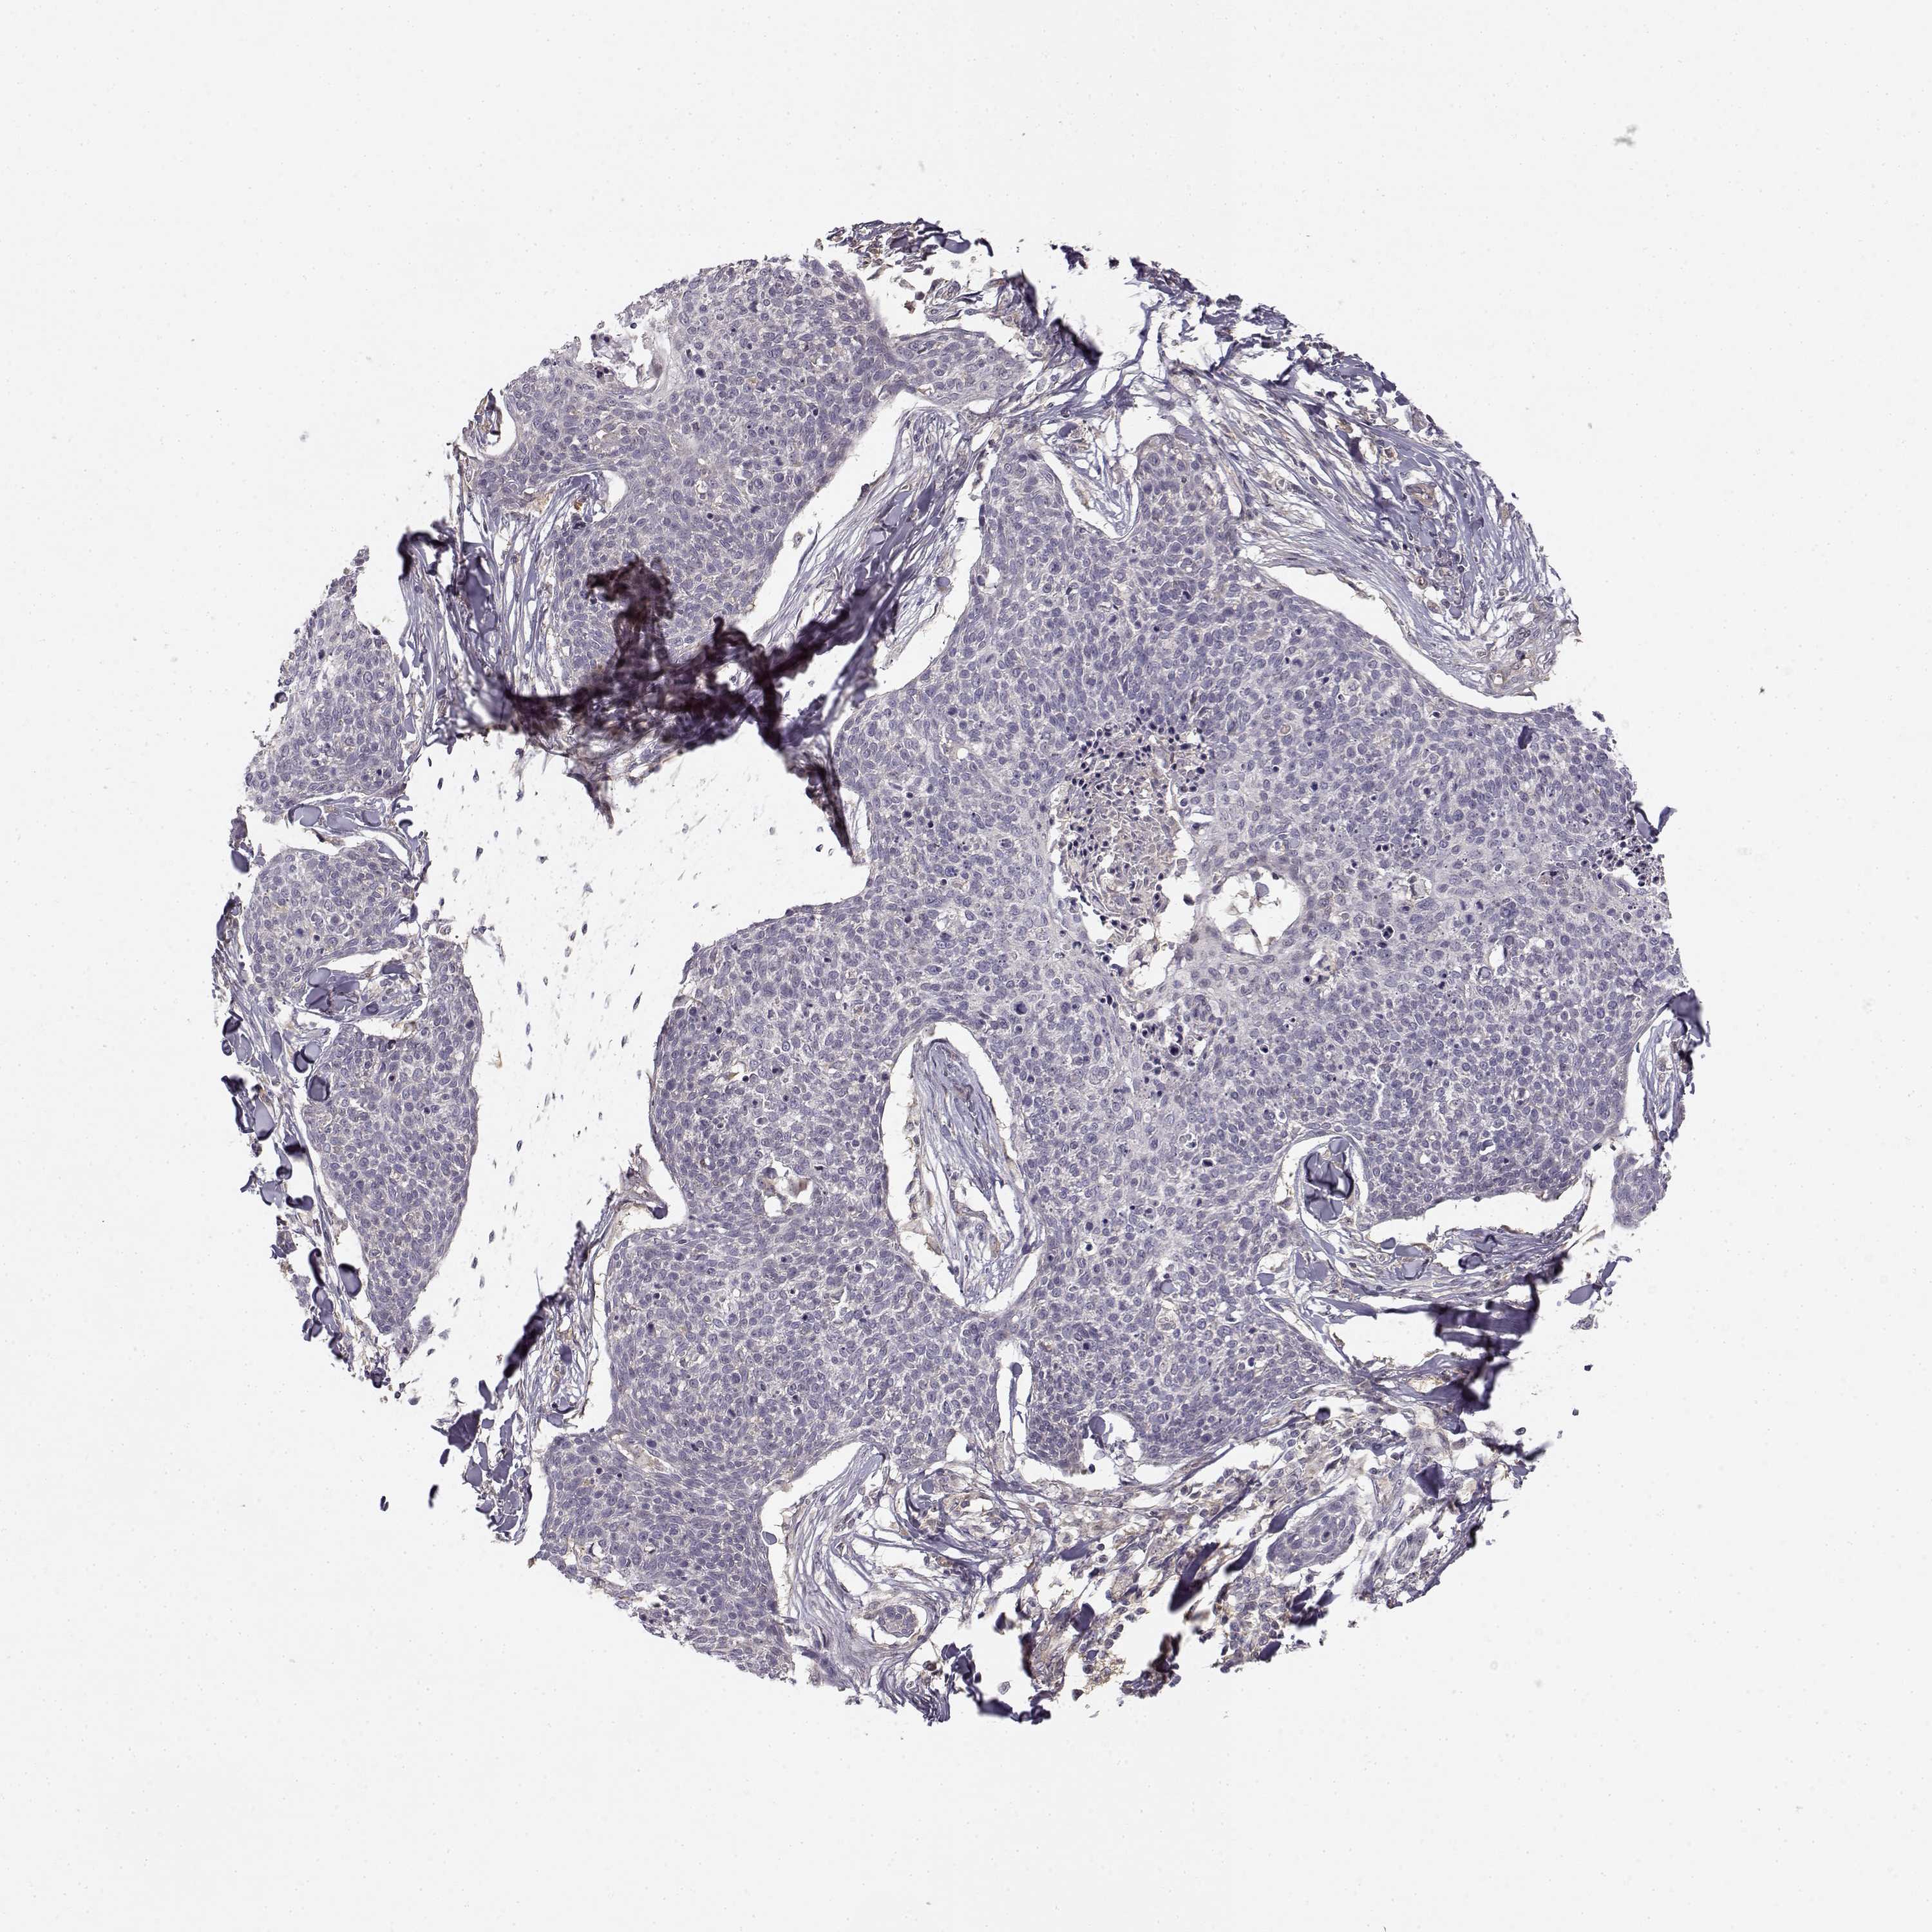

Basal cell and squamous cell cancer

SKIN CANCER - Protein expressioni

A mouse-over function shows sample information and annotation data. Click on an image to view it in a full screen mode. Samples can be filtered based on level of antibody staining by selecting one or several of the following categories: high, medium, low and not detected. The assay and annotation is described here.

Antibody stainingi

Antibody staining in the annotated cell types in the current human tissue is reported as not detected, low, medium, or high, based on conventional immunohistochemistry profiling in selected tissues. This score is based on the combination of the staining intensity and fraction of stained cells.

Each image is clickable and will lead to virtual microscopy that enables deeper exploration of all samples and also displays staining intensity scores, fraction scores and subcellular localization as well as patient and tissue information for each sample.

Antibody HPA036807

Staining

High

Medium

Low

Not detected

Intensity

Strong

Moderate

Weak

Negative

Quantity

>75%

75%-25%

<25%

None

Location

Nuclear

Cytoplasmic/membranous

Cytoplasmic/membranous,nuclear

Basal cell carcinoma

Squamous cell carcinoma, NOS